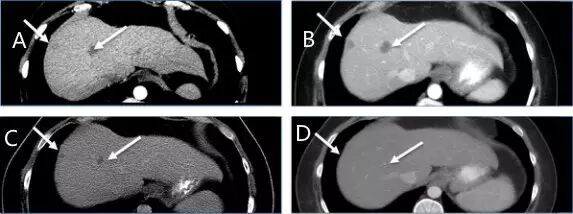

治疗1个月奇迹出现了,CT显示M女士纵隔淋巴结肿大缩小,没有新的肝或纵隔病变(图1A和B和2A和B与图1C和2C),并且在3个月时的影像学检查显示出纵隔淋巴结肿大和肝脏局部病变进一步缓解(图1D和2D)。8个月的影像显示纵隔淋巴结持续缩小,肝脏病变完全消退(图1E和2E)。患者目前仍继续进行治疗。

图1:ABCDE